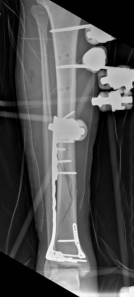

Initial management in these high-velocity scenarios mandates the application of a spanning external fixator to achieve skeletal traction, restore length, and allow the soft tissue envelope to recover. This temporary stabilization minimizes ongoing secondary soft tissue trauma from mobile fracture fragments. However, the application of external fixators is not without risk; meticulous pin placement is required. For instance, calcaneal transfixion pins must be placed with strict attention to the neurovascular bundle to avoid iatrogenic tibial nerve irritation, an issue that required revision in the early phase of our index patient's care.